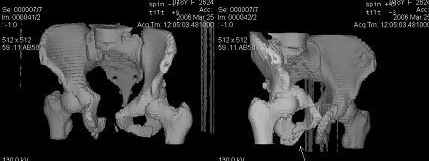

Уважаемые коллеги! Девушка 18л сросшиеся переломы лонных, седалищных костей с обеих сторон, перелом крестца справа,перелом костей голени справа (зио), 3 мес после травмы, АВФ снят с таза. Патологической подвижности нет. Стоит самостоятельно, ходит с костылями, поскольку 3 месяца практически не ходила. Беспокоит выступание лонной кости в области лобка, хотя объективно грубого косметического дефекта нет. На кт разворот лонной кости в сагиттальную плоскость. Вопрос: стоит ли добиватьсяполной репозиции или же достаточно произвести остеотомию верхушки выступающего отломка?

Предварительный диагноз- посттравматическая вертикальная нестабильная деформация таза II степени, неправильно срастающийся перелом боковой

массы крестца справа, правой лонной и седалищной костей, застарелый разрыв лонного сочленения.

Для уточнения диагноза ниеобходимы обзорные рентгенограммы таза (прямая и inlet), Кт срезы на уровне переломов для определения степени сращения и решения вопроса о методе оперативного восстановления анатомии (делать ли остеотомию, низводить ли задние отделы), ни о какой "остеотомии выступающих отломков" тем более у девочки 18 лет речи быть не может.